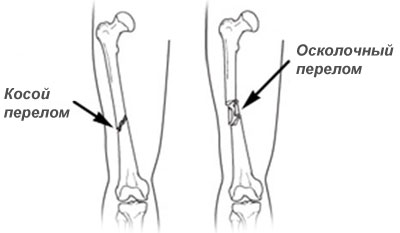

Виды заболевания

Переломы шейки бедренной кости подразделяют на трансцервикальные, базальные и субкапитальные. В зависимости от механизма возникновения травмы они могут быть абдукционными и аддукционными (встречаются более часто).

Линия перелома может находиться за пределами сустава (внесуставной перелом) или проходить внутри его (внутрисуставной перелом).

Выделяют следующие виды внутрисуставного перелома бедра:

- капитальный - линия перелома расположена в области головки бедра;

- трансцервикальный (чрезшеечный) - линия перелома проходит в области шейки бедра;

- субкапитальный - линия перелома расположена под головкой;

- базисцервикальный - линия перелома проходит на границе перехода шейки в тело бедренной кости.

Внесуставные переломы в верхней части бедра расположены на уровне вертелов. Различают межвертельные и чрезвертельные переломы.

При переломе тела (диафиза) бедренной кости выбор метода операции зависит от вида перелома. Использование интрамедуллярного (внутрикостного) или накостного методов фиксации определяется индивидуально.